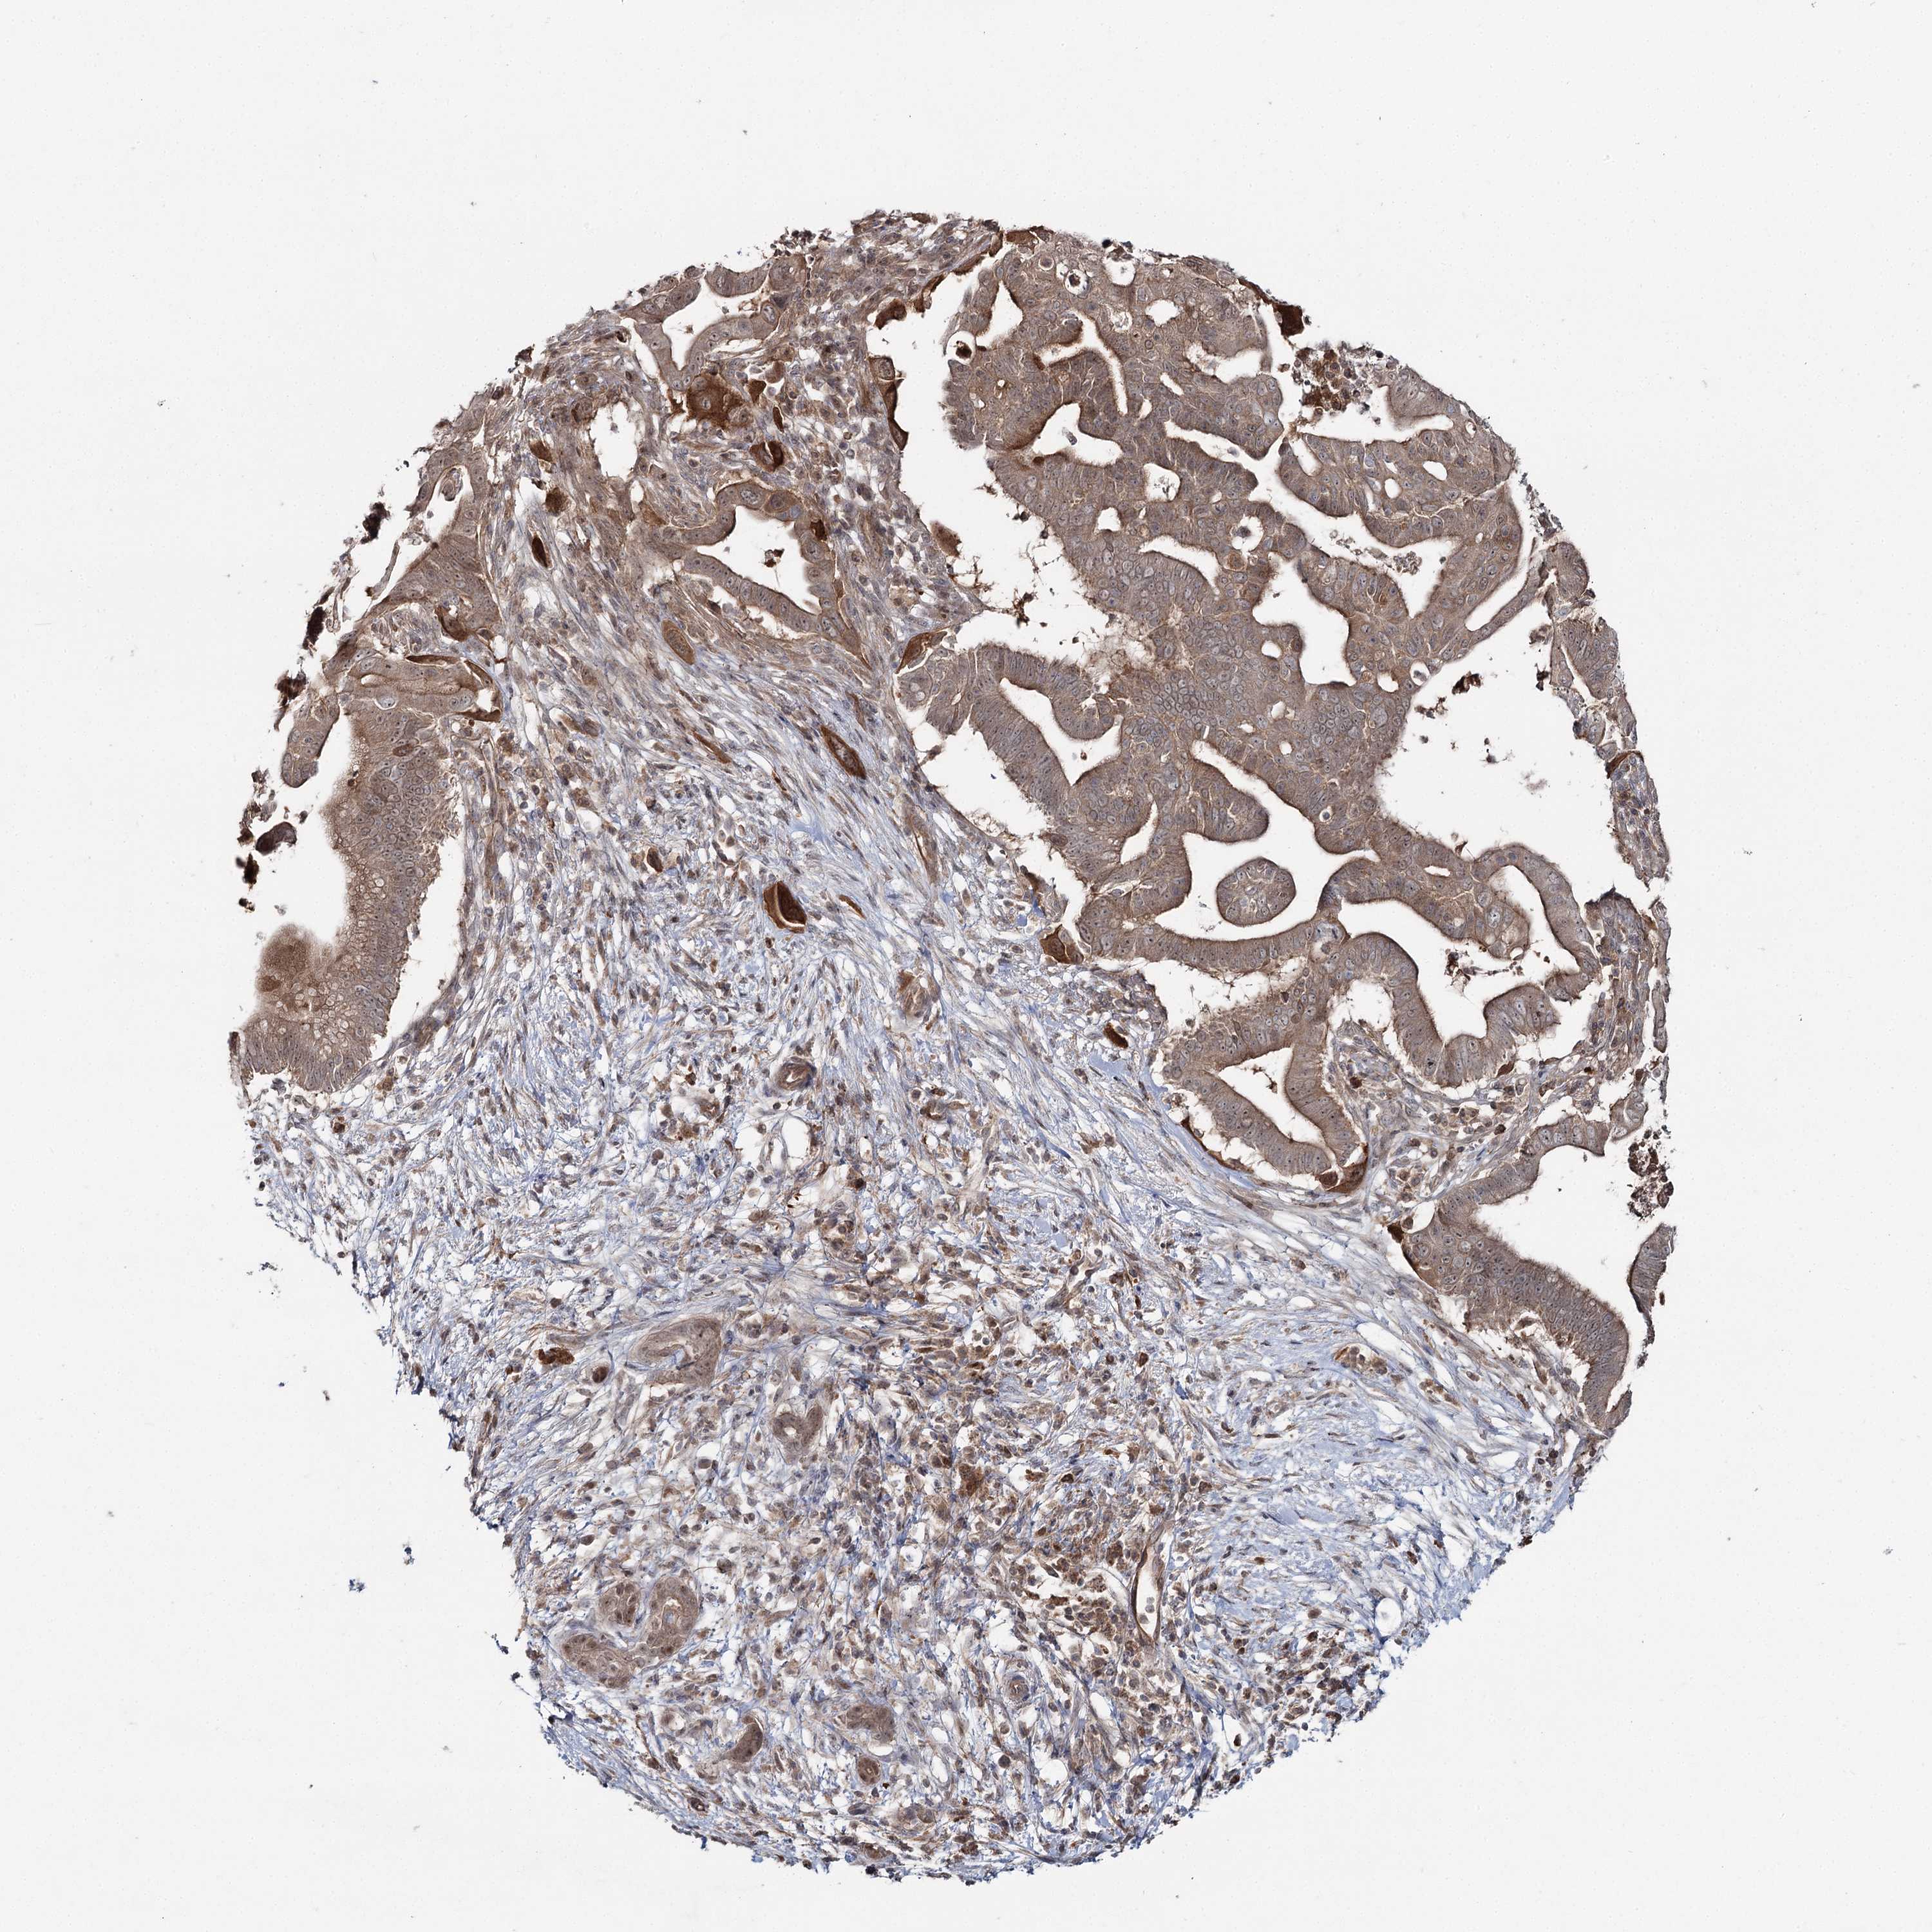

PANCREATIC CANCER - Protein expressioni

A mouse-over function shows sample information and annotation data. Click on an image to view it in a full screen mode. Samples can be filtered based on level of antibody staining by selecting one or several of the following categories: high, medium, low and not detected. The assay and annotation is described here.

Note that samples used for immunohistochemistry by the Human Protein Atlas do not correspond to samples in the TCGA dataset.

Antibody stainingi

Antibody staining in the annotated cell types in the current human tissue is reported as not detected, low, medium, or high, based on conventional immunohistochemistry profiling in selected tissues. This score is based on the combination of the staining intensity and fraction of stained cells.

Each image is clickable and will lead to virtual microscopy that enables deeper exploration of all samples and also displays staining intensity scores, fraction scores and subcellular localization as well as patient and tissue information for each sample.

Antibody HPA038084

Staining

High

Medium

Low

Not detected

Intensity

Strong

Moderate

Weak

Negative

Quantity

>75%

75%-25%

<25%

None

Location

Nuclear

Cytoplasmic/membranous

Cytoplasmic/membranous,nuclear

Adenocarcinoma, NOS